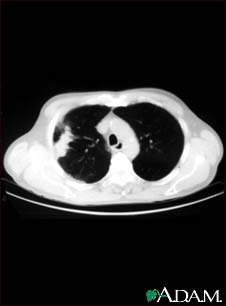

Lung with squamous cell cancer - CT scan

This CT scan shows a cross section of the lungs of a person with lung cancer. The two dark areas in the middle of the screen are the lungs. The light areas in the right lung represent the cancer (left side of picture).